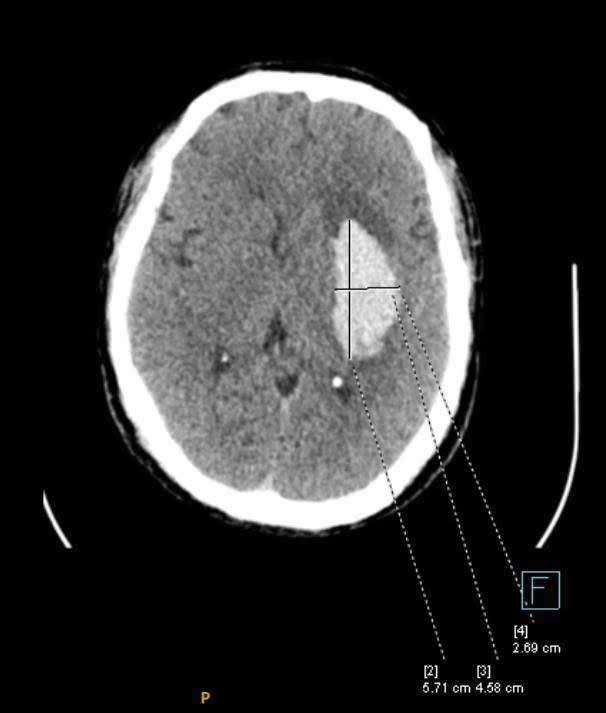

Một trường hợp cấp cứu đột quỵ của bác sĩ Nguyễn Thắng Nhật Tuệ vì bệnh nhân thường xuyên bỏ thuốc huyết áp. (Nguồn ảnh: Page “Một ngày ở viện”)